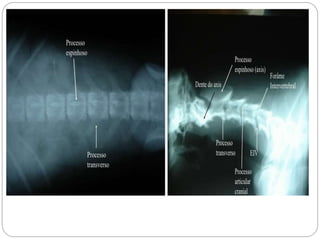

Figura – 3

Látero-lateral oblíqua de

boca aberta